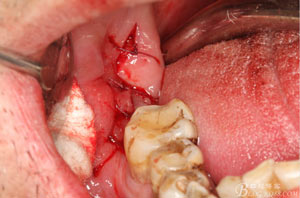

圖9.高速牙鉆分牙:

圖10.先頰舌向橫斷、然后再把牙冠近遠(yuǎn)中向縱分

圖11. “T”型的分牙。